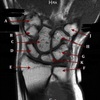

What is letter A?

HAMATE

68

What is letter B?

CAPITATE

69

What is letter C?

TRAPEZOID

70

What is letter D?

TRAPEZIUM

71

What is letter E?

MEDIAN NERVE

72

What is letter F?

FLEXOR TENDONS